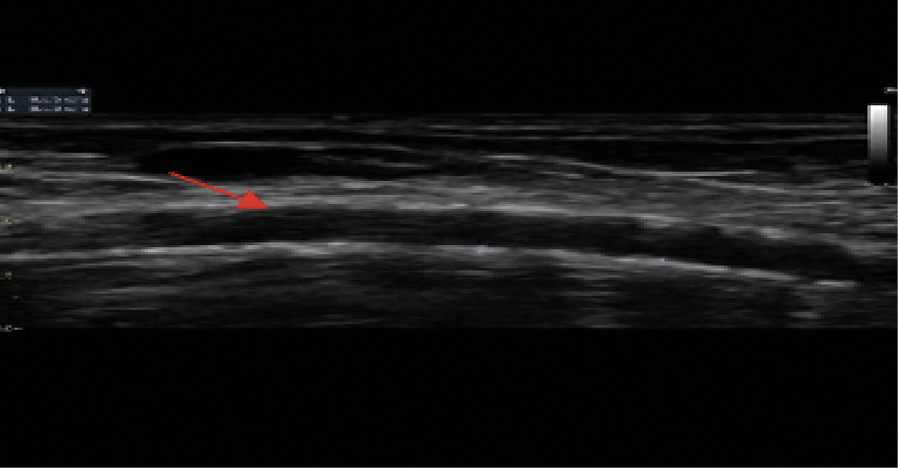

Рис. 5. Эхограмма пациента Т. Ультразвуковое дуплексное сканирование артериовенозной фистулы левой верхней конечности. Обызвествление стенок плечевой артерии артериовенозной фистулы левой верхней конечности (указано стрелкой)